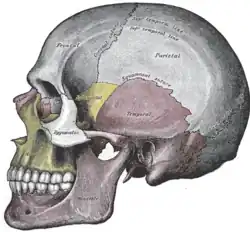

Visão lateral animada.

Osso lacrimal isolado. Visão lateral.